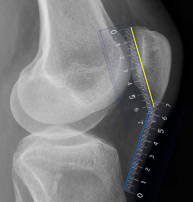

Q what is the name of this measurement? and what is the average + range?

A: Patellar Position

assesses the position of the patella using a ratio of patellar length (PL) to patellar tendon length (PT). The ratio is normally 1:1, with a variation of up to 20%.